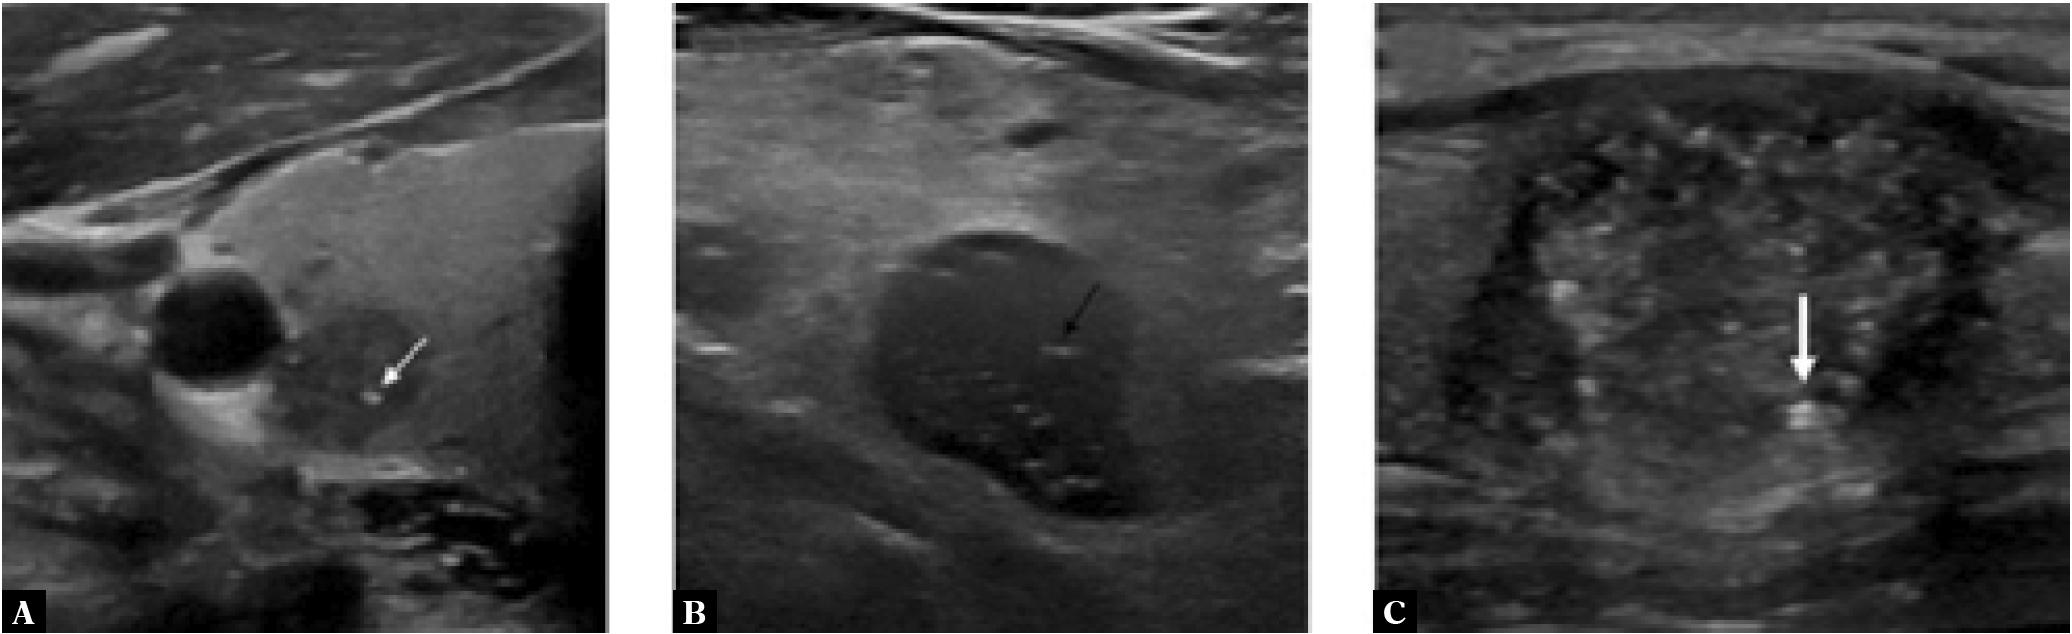

Unlike macro-calcifications, neither of these sonographic observations are associated with posterior acoustic shadowing. Punctate echogenic foci (PEF) are round and ≤1 mm, while echogenic interfaces have a linear or tram like appearance (Fig. 1). Large echogenic foci >1 mm associated with comet-tail artifacts (+0 points) denote colloids, and are benign. In contrast, echogenic foci ≤1 mm with comet-tail artifacts should be treated as PEF (+3 points)(4). Pertinently, if echogenic foci are found both in the nodule and in the surrounding thyroid parenchyma, these should not be classified as PEF(4). Benign observations that can mimic PEF include the back wall of tiny cysts and speckle pattern in normal thyroid parenchyma(4).

Fig. 1

Greyscale sonographic images of: A. a thyroid nodule with round punctate echogenic foci (white thin arrow); B. a thyroid nodule with linear echogenic interfaces (black arrow); and C. a thyroid nodule with echogenic foci demonstrating a comet-tail artifact, in keeping with a colloid (white thick arrow)